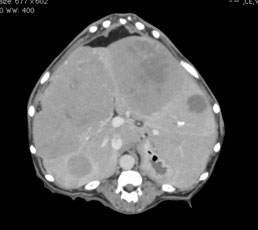

主訴:1年前から肝臓に腫瘍が認められており、お腹が膨れてきて元気食欲ともになくなってきたため、他の病院からの紹介で来院されました。超音波検査およびCT検査にて肝臓内側右葉および外側右葉に巨大な肝臓腫瘍が認められました。

CT検査:肝臓内に腫瘍が確認されました。